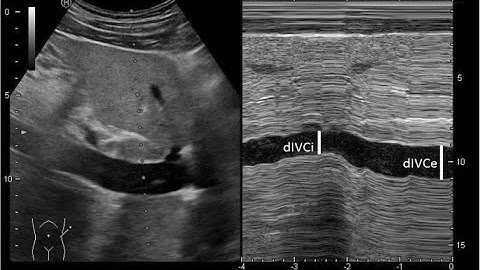

Methods of measuring fluid responsiveness